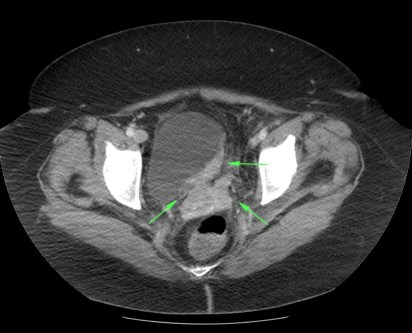

- Realce temprano por TC con contraste y cortes finos: algunos autores defienden que también habría que examinar la vejiga mediante la obtención de imágenes en una fase previa (60 -80 seg.) tras la inyección de contraste ya que el cáncer de vejiga muestra un realce precoz que es mayor que el de la pared vesical normal. Además de la fase excretora, esta fase precoz es una herrmienta útil que podemos usar, si bien no de manera sistemática, por lo menos ante determinados casos según cuando el riesgo clínico es elevado o tenemos hallazgos en otras pruebas, como una ecografía, los cuales podríamos analizar de una manera más dirigida.

EXTENSIÓN:

Estadíos:

- T1: Invaden la lamina propia.

- T2: Invaden las capas superficiales del músculo.

- T2b: Invaden las capas profundas del músculo.

- T3a: Extensión perivesical microscópica.

- T3b: Extensión macroscópica.

- T4: Invaden órganos vecinos o la pared pélvica.

La realización de una uro-TC o un TC de vejiga tiene limitaciones a la hora de realizar la estadificación ya que no podemos distinguir el cáncer No músculo invasivo del que sí lo invade y, además, no podemos detectar mediante TC la invasión microscópica perivesicual del tumor que constituye el estadio T3a. La deteción de un tumor macroscópico (T3b) también puede ser problemática, solo son calramente visibles cuando la extensión es de tipo Bulky.

La extensión al tejido blando perivesical es un hallazgo no específico que puede ser debido a un tumor o al marcado edema, especialmente si la uro-TC se realiza en la primera semana post resección transuretral, ya que los cambios reactivos perivesicales son mayores en este periodo.